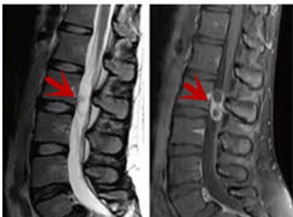

利器三:MRI(核磁共振)

MRI利于磁場和射頻脈沖使體內(nèi)的氫原子核發(fā)生磁共振現(xiàn)象而產(chǎn)生的圖像,對軟組織的分辨率很高,對于脊髓、椎間盤、神經(jīng)、血管、韌帶、骨髓、腰部肌肉及周圍軟組織有很好的顯示效果,可以清晰的顯示腰椎間盤突出對硬膜囊、神經(jīng)根壓迫程度,以及骨折是陳舊還是新鮮,同時在脊髓病變(如脊髓損傷、髓內(nèi)出血或腫瘤)、椎管內(nèi)膿腫/血腫、椎旁肌肉軟組織病變等方面也具有優(yōu)勢,但是檢查時間較長,部分患者可能因體內(nèi)金屬植入物(如心臟起搏器、人工耳蝸等)而無法進行檢查。

箭頭提示腰椎管內(nèi)腫瘤

紅色箭頭提示新鮮骨折,黃色箭頭提示陳舊性骨折